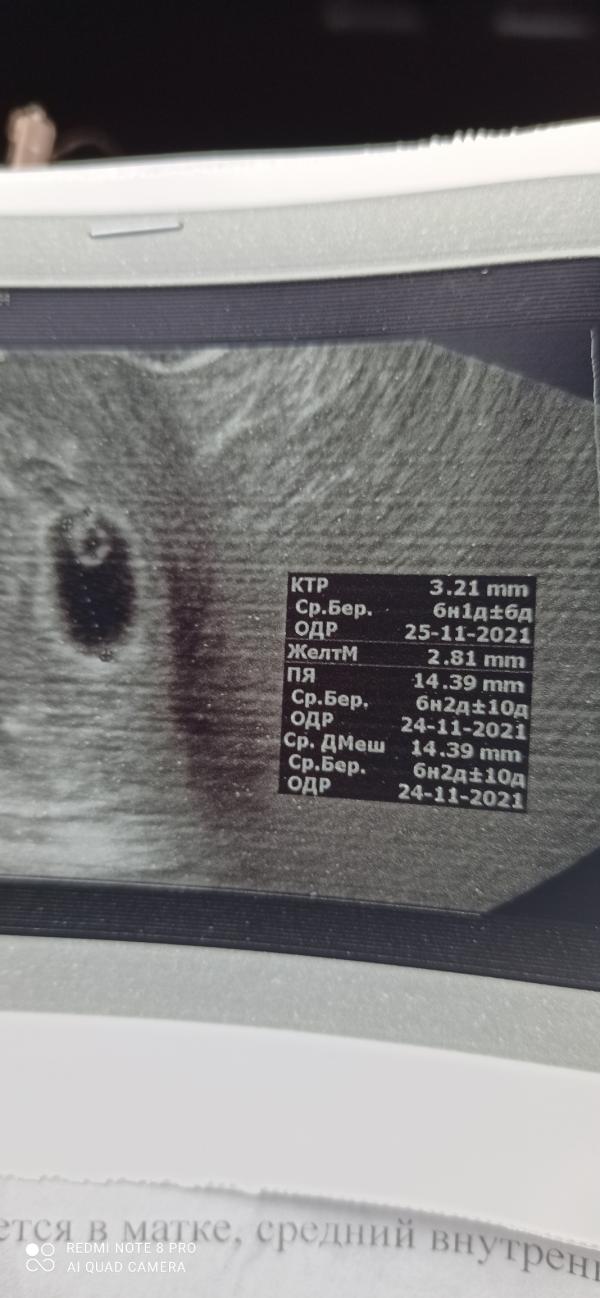

ПЯ растет, появился эмбриончик) А самое главное сердечко стучит ❤